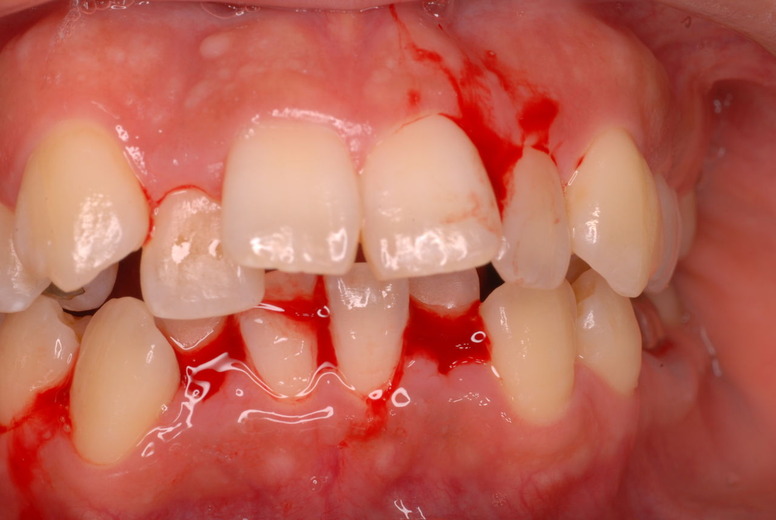

親知らずを取ることを嫌がる方が多いのですが、もし親知らずとその隣の14歳大臼歯の間に虫歯ができたり歯周病を罹患した場合、どれほど治療が大変で再発も起こりやすいか理解できない方がおおいのです。

写真左下の親知らずが痛くなり抜歯しました。その後歯茎を除去して虫歯を露出させる処置を二回ほどしています。

レントゲンでは小さいですが、こう言う虫歯が一番怖いのです。

治療の成功率は極めて悪くすぐ再発しやすいのです。